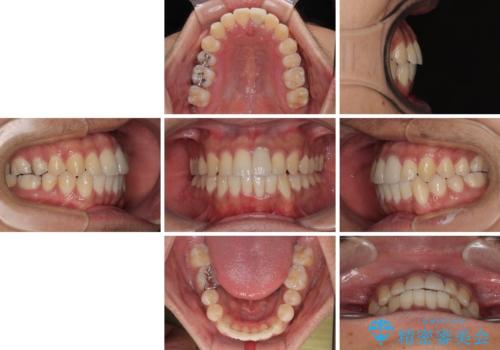

気になる前歯のデコボコと八重歯 ワイヤー矯正ですっきりと

矯正治療後には気になっていた前歯をセラミッククラウンにし、自然な口元に仕上げることができました。